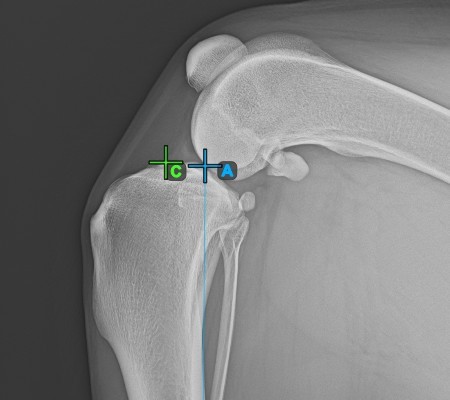

Start the measurement by marking the Eminentia Intercondylaris, which is located on the joint connecting the femur and the tibia.

The image below depicts the usual placement of the Eminentia Intercondylaris point.

../../_images/image224.jpg